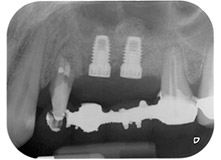

Fig. 1: 58-year-old patient. Preoperative radiograph showing an apical periodontal lesion at tooth 24 and horizontal loss of alveolar bone in the second quadrant.

A 58-year-old female patient complained of pain and increased mobility of her bridge abutment tooth 24. Periodontal inflammation was present with pocket depths of 7 mm mesiobuccally and more than 12 mm distally, as well as third-degree furcation involvement. Moreover, the radiograph revealed an extensive periodontal lesion around the apical region of the (alio loco) endodontically pretreated tooth 24 (Fig. 1).

One year earlier, teeth 25 and 26 had been extracted due to trauma and for endo-perio reasons, prior to the placement of the bridge. A combined endo-perio lesion was diagnosed for tooth 24, of unclear aetiology. The patient wanted to keep her bridge abutment teeth 24 and 27 and would not accept a final, or even temporary, removable prosthesis. Therefore, it was agreed to make all efforts to retain both teeth, in spite of their poor prognosis as based on radiological and clinical findings.

Placement of two submerged implants was planned at sites 25 and 26, in a surgical session with open periodontal debridement and apicoectomy of tooth 24. Due to the vertical bone deficiency at the future implant site, an internal sinus augmentation was also planned.

Finally, after periosteal incision, the site was passively sutured with a coronally advanced flap, using 5-0 absorbable suture material (Fig. 15). The postoperative radiograph showed both implants in their correct vertical position (Fig. 16).

Postoperative radiograph

Fig. 16: Postoperative radiograph showing the implants in place, with bone substitute material from the internal sinus lift around the apices. There is some material from the GTR procedure visible around the roots of tooth 24.